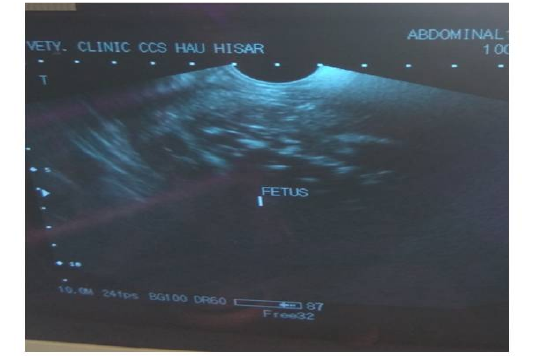

Figure 1

Ultrasonographic image of mummified fetus in animal No. 2